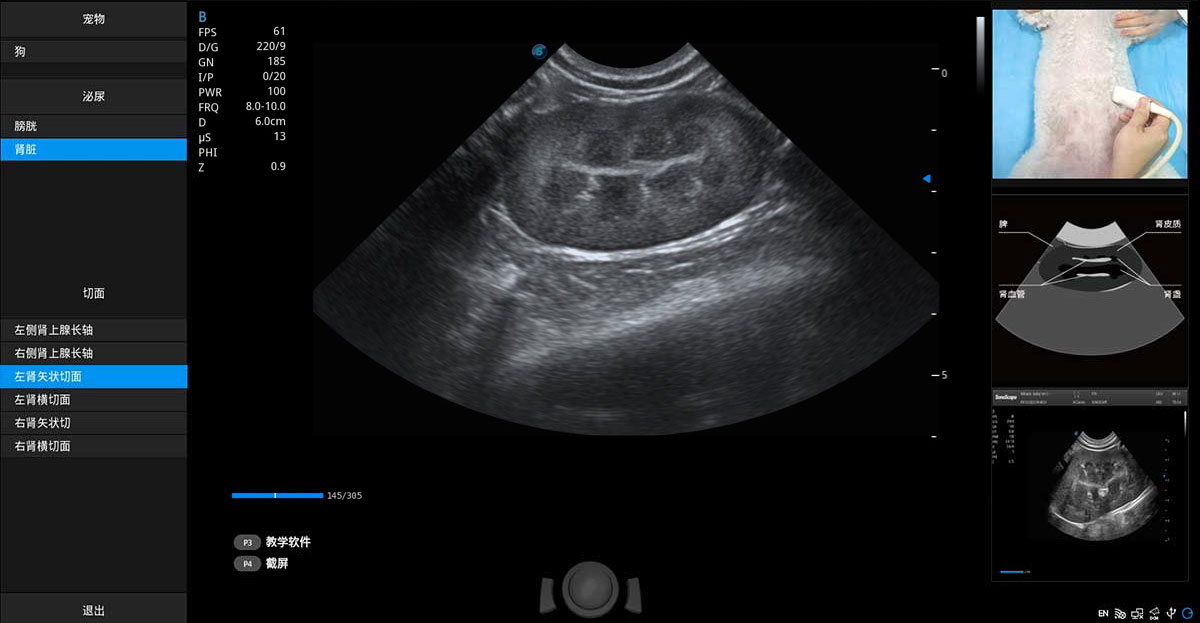

提供解剖示意圖、標(biāo)準(zhǔn)超聲圖像、掃查手法圖和操作者實(shí)時(shí)檢查圖像,指導(dǎo)操作者進(jìn)行標(biāo)準(zhǔn)切面的正確掃查。